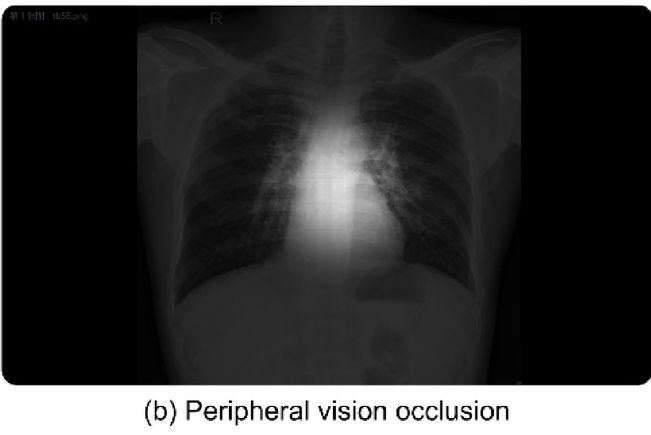

Schill's group recruited 34 radiologists and exposed them to multiple series of mammograms that included abnormalities using a method called repeated imaging with single evaluation, or RISE. (This technique presents subjects with images that repeat in an unpredictable order with varying levels of noise, ensuring that any biases are visual rather than cognitive.) In some of the image sets, the mammograms were blurry and became clearer as the study continued; in others, the exams were clear and became blurrier. Readers were prompted to decide whether the abnormality in the image was a mass or a calcification and to rank their confidence in this categorization.

The team theorized that those readers who saw clear images first would respond more accurately and confidently with the blurry versions of the same images due to visual hindsight bias. The study findings in fact supported this, suggesting that prior information gained from viewing the clearer images allowed radiologists to assess blurrier images more accurately, SPIE said in its statement.